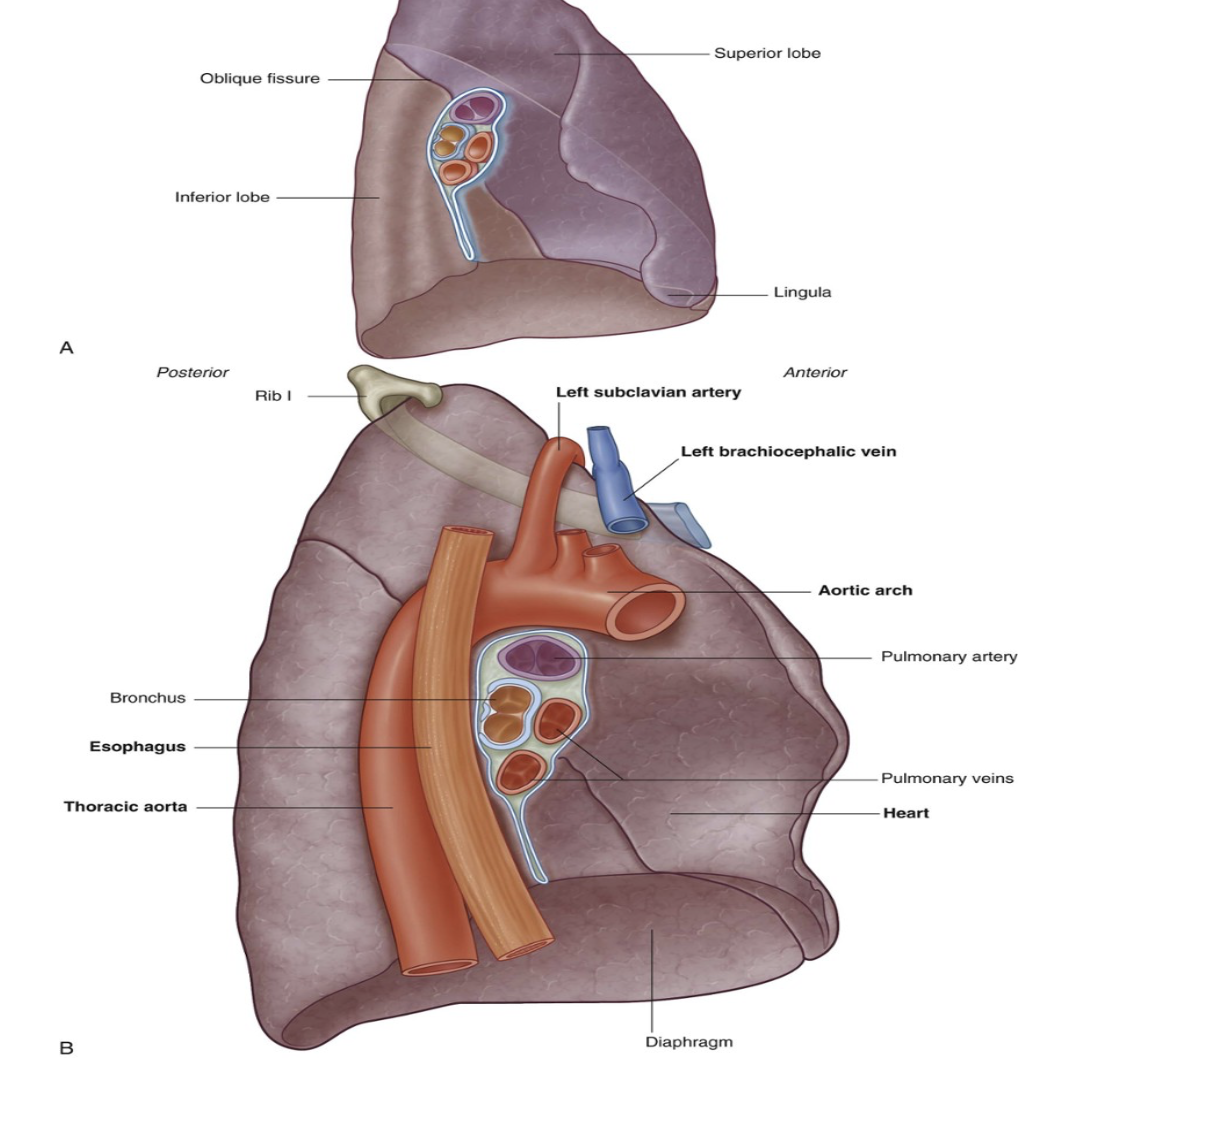

Left lung lobes & fissure

2 — superior & inferior, with fissure separating them

Superior lobe —

In contact with upper part of anterolateral wall & apex of this lobe projects into the root of the neck contact

Costal surface of inferior lobe — in contact with posterior & inferior walls

Oblique fissure —

Separates superior & inferior lobe — slightly more oblique than that on right lung

Left lung is slightly smaller than right lung due to heart on left side (thus left lung has corresponding cardiac notch & additionally the associated lingula of the left lung which projects over the heart bulge

Important structures in the mediastinum & root of neck that are adjacent to medial surface of left lung

Heart

Aortic arch,

Thoracic aorta

Esophagus

Note about subclavian vessels & left lung

The left subclavian artery and vein arch over and are related to the superior lobe of the left lung as they pass over the dome of the cervical pleura and into the axilla